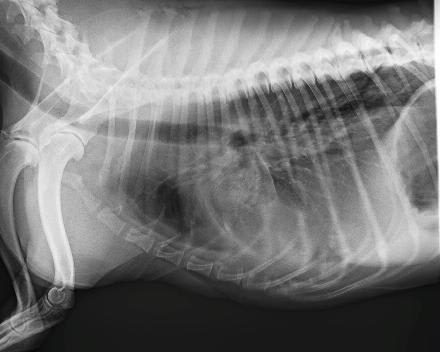

My dog has had a cough for over a month. They said her blood work and xray seem normal. I feel like her breathing is getting a bit worse. Her resting rate is about 35 bpm. She's on doxycioline which doesn't seem to be helping.

You might ask your veterinarian if the X-rays could be reviewed by a radiologist. While the resolution that the forum pictures allow makes them a bit difficult to interpret, I am concerned that the X-rays do not appear normal, and she may have a more serious underlying condition. It may be that she has some underlying heart disease, cancer, or an infection that requires a more broad spectrum of antibiotic. I agree the blood work you've attached is unremarkable. Was a CBC performed as well? Check back with your vet about a radiology review, and a recheck exam as well. A consult with a cardiologist may be recommended, depending on the radiologist's opinion. I'm sorry I don't have better news, or a solution to offer you to try at home, but I think you need to circle back and followup with your vet on this. Thank you for asking Petco Pet Education Center, formerly Petcoach.